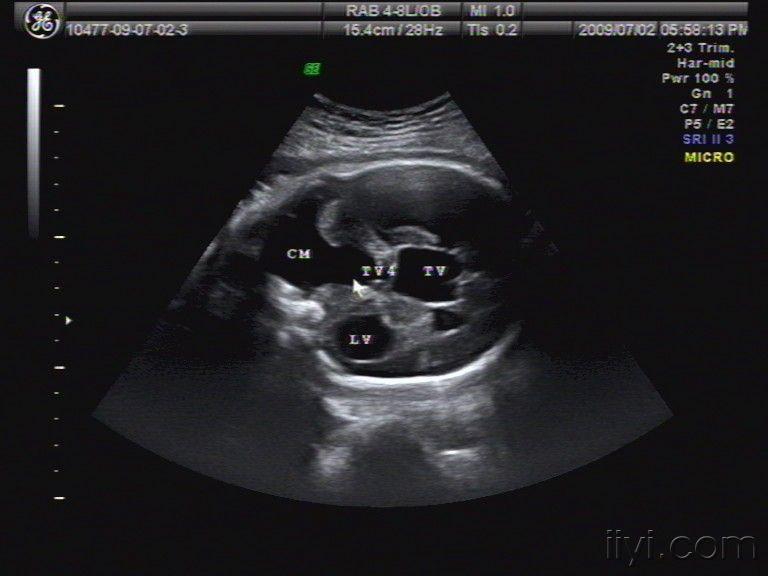

产科畸形-dandy-walker综合征 - 超声医学讨论版 - 爱爱医医学论坛

图片尺寸768x576